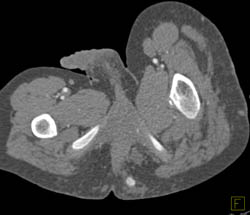

Cellulitis